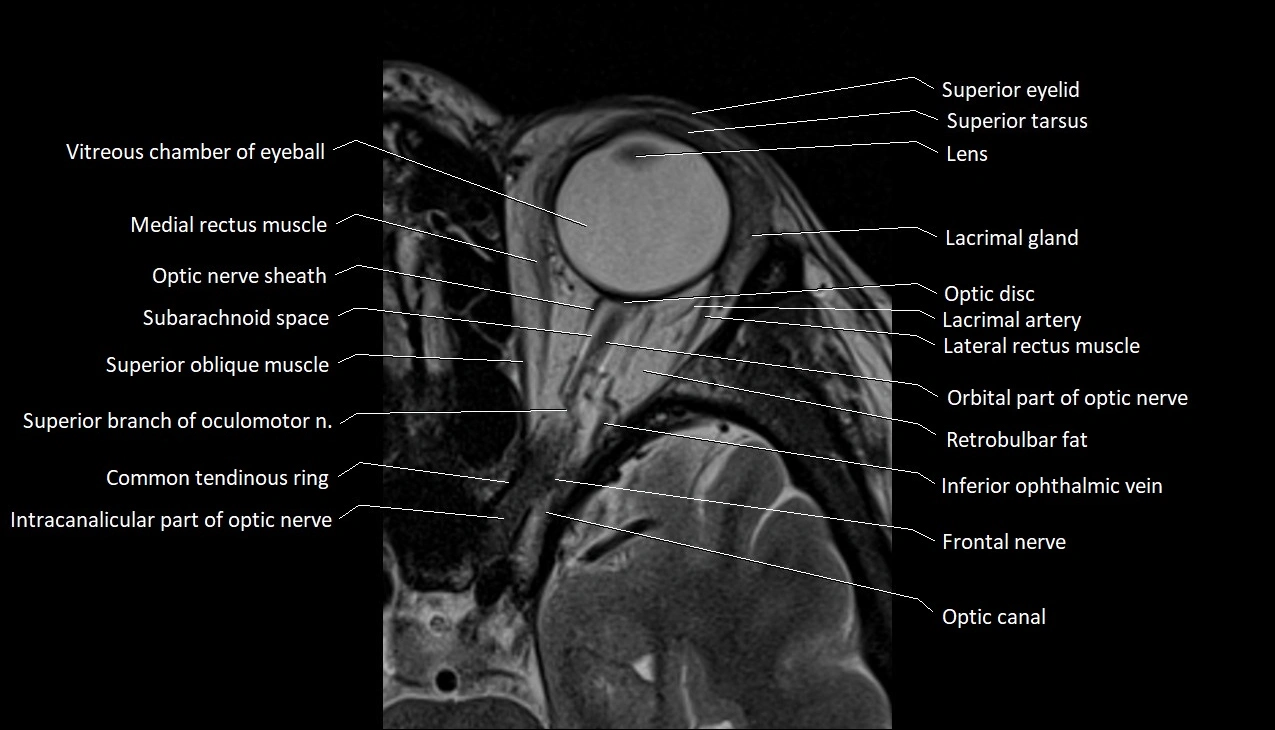

- Common tendinous ring (Annulus of zinn)

- Frontal nerve

- Inferior ophthalmic vein

- Intracanalicular part of optic nerve

- Lacrimal artery

- Lacrimal gland

- Lateral rectus muscle

- Medial rectus muscle

- Oculomotor nerve (Superior branch)

- Optic canal

- Optic disc

- Optic nerve sheath

- Orbital part of optic nerve

- Retrobulbar fat

- Subarachnoid space of optic nerve

- Superior eyelid

- Superior oblique muscle

- Superior ophthalmic vein

- Superior tarsus

- Vitreous chamber of eyeball

- Whitnall's ligament